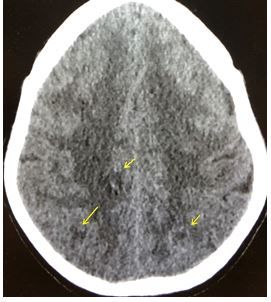

Imaging: A CT scan is done of the head. The cut shown below includes yellow arrows highlighting abnormalities.